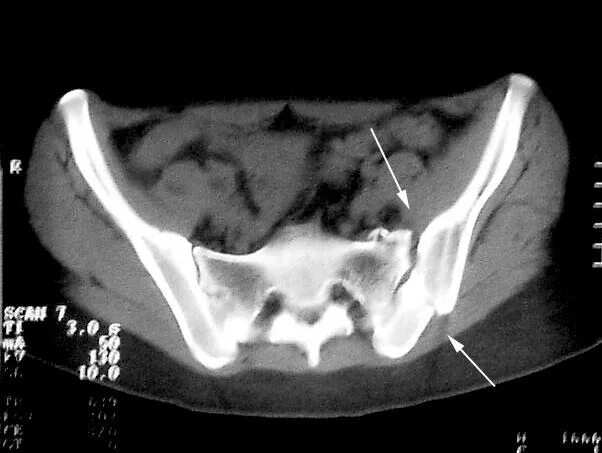

Воспаление подвздошных сочленений